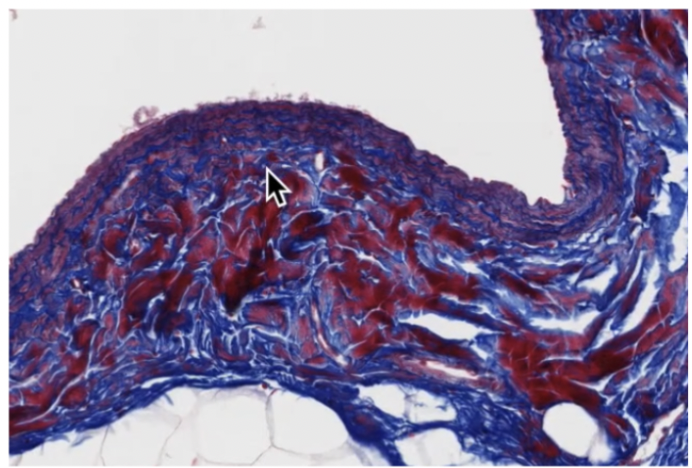

Medium veins

Thin tunica intima and media but thick tunica adventitia

medium vein with valve

Irregularly dispersed smooth muscle

No internal elastic lamellae

Valves are the extensions of tunica intima to break into small compartments for movement (skinny extensions in photo)